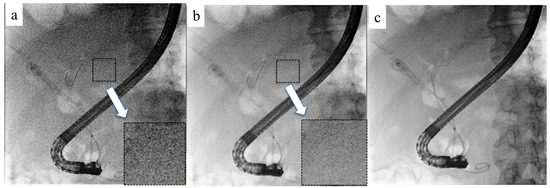

Recursive filtering is a conventional technique that reduces image noise and improves observation by combining the past fluoroscopic image with the current one [32]. However, this method can cause blurring when there is motion in the subject. To address this, ANR was developed. ANR reduces image noise by appropriately switching between two noise filters using different reduction methods based on the correlations between the target pixel and its surrounding pixels (Figure 2) [33]. Combining recursive filtering with ANR effectively reduces noise. However, motion blur caused by respiratory variation is not detected, making image processing challenging in the presence of motion blur induced by respiratory variation.

Figure 2. Adaptive noise reduction (ANR). (a) Before the introduction of ANR. Numerous noises are shown in the magnified field. (b) After the introduction of ANR. Noises are reduced, and the image is clearer in the magnified field. (c) ANR combined with a recursive filter.